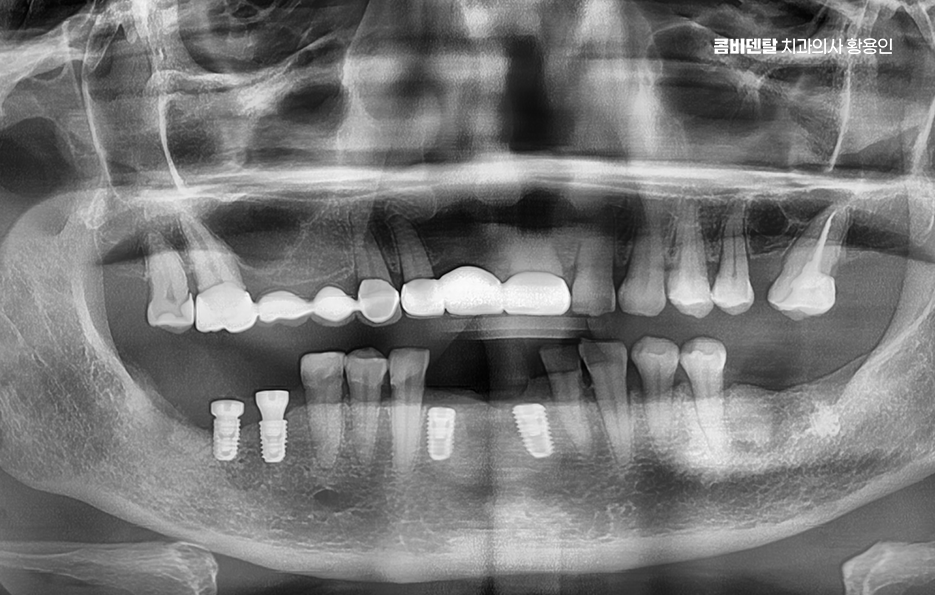

임플란트의 장점 이 골유착이 완성된 이후에는 그 위에 기둥을 세우고, 마지막으로 보철물을 씌우게 되는데 이렇게 되면 겉에서 보기엔 자연치아와 거의 차이가 없으며 심지어 기능적으로도 자연치아와 유사한 수준의 저작력이 가능해지며 다시 말해 뿌리부터 머리까지 인공치아를 만드는 건데 ‘뼈에 심는’ 것이기 때문에 더 안정적이고 오래 쓸 수 있는 치료인 거예요.

이러한 치료 원리를 토대로 임플란트의 장점을 정리해보면 첫 번째로 큰 장점은 주변 치아에 손상을 주지 않는다는 점으로 예전에는 치아를 하나 잃으면 양 옆의 치아를 깎아서 브릿지를 씌우는 방식이었어요. 문제는 건강한 치아까지 손상시켜야 한다는 점이었고 게다가 브릿지 아래는 관리가 어렵다 보니 2차 충치가 생기기 쉬워서 결국 더 많은 치아를 잃게 되는 경우가 많았던 것인데 임플란트는 해당 부위만 단독으로 치료하기 때문에 주변 치아는 그대로 두고, 본인 치아처럼 기능하게 할 수 있었어요.

또한 임플란트는 잇몸 뼈에 고정돼 있어서 씹는 힘이 자연치아의 80~90%에 가까울 정도로 강하고, 사용하면서도 불편함이 거의 없다는 장점이 있는데 틀니와는 비교가 어려운 씹는 힘을 복원할 수 있고 개별 치아를 대상으로 치료가 가능하다는 임플란트의 장점은 현재 임플란트가 도입된 이후에 빠르게 대중화된 대표적인 이유라고도 볼 수 있어요

또한 요즘은 임플란트 기술이 점점 더 정밀해지고 빨라지고 있는데 예전에는 임플란트 식립 후 몇 달을 기다려야 보철을 올릴 수 있었지만 현재는 뼈 상태나 환자 조건이 좋으면 즉시 식립 임플란트가 가능한 사례가 크게 늘어 났고 이러한 치료 방식은 치아를 뽑고 그 자리 임플란트를 당일에 바로 심는 방식인데 시술 횟수도 줄고 회복 시간도 단축돼서 바쁜 직장인들에게도 부담이 덜해졌어요.